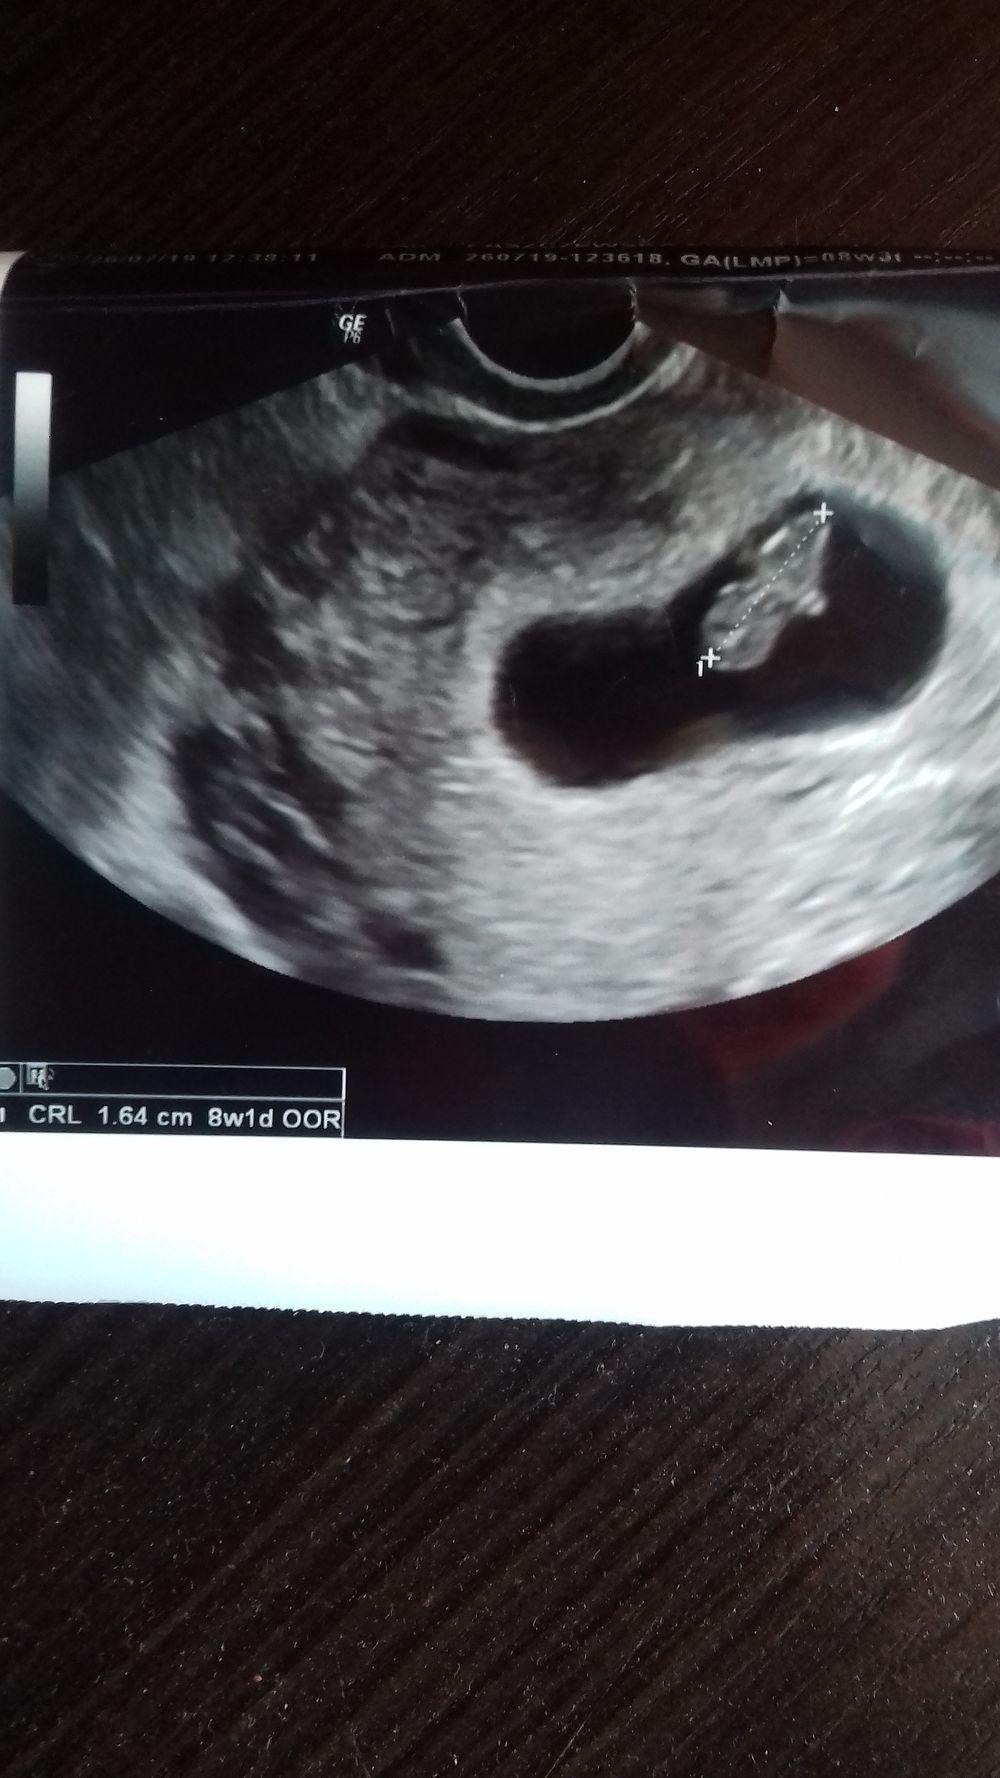

Witam i ja . Dziś tez miałam wizytę prywatnie. Termin na 5.03.2020 . Dzidzia ma już 1.64 cm i jest to 8tc1d.

Oto dzidzia.